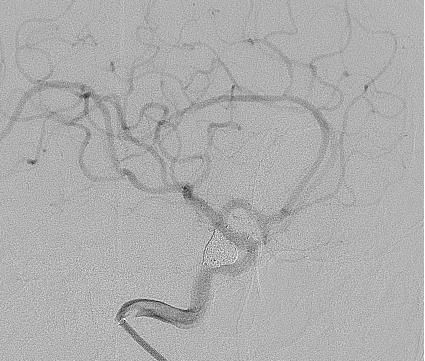

榕山镇70岁的胡婆婆因突发头颈部疼痛入住我院。急诊头颅CT显示广泛蛛网膜下腔出血,经验丰富的神经外科医生立即意识到是可怕的颅内动脉瘤破裂出血。经过脑血管造影检查证实,果然是右侧后交通动脉瘤破裂出血

图片

情况更加复杂的是,动脉瘤体大、瘤颈宽、形态不规则,随时都有再次破裂出血的危险。胡婆婆年龄较大,身体瘦弱,基础条件差,开颅手术耐受能力极差。在充分评估病情与患者家属深入沟通后,科室一致决定为胡婆婆进行微创手术。

神经外科介入团队迅速启动绿色通道手术预案,由侯黎明主任医师与汪棋笙副主任医师主刀,在李华国主治医师协助下行了微创颅内动脉瘤支架辅助介入栓塞术。经过数小时手术,成功栓塞了动脉瘤,解除了再次出血风险。